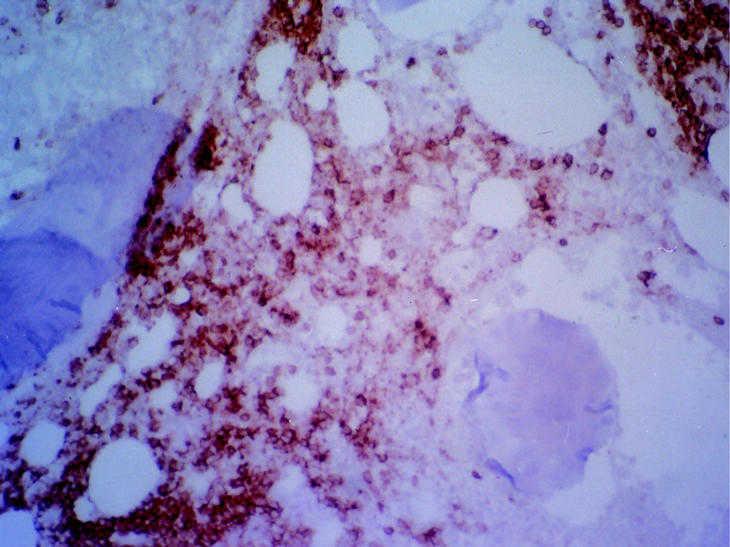

Fig. 3. Mucosa del intestino delgado con extensa atrofia vellositaria. En el ámbito de la lámina propia destaca un infiltrado tumoral de carácter linfoide con patrón difuso constituido por células grandes con núcleos hipercromáticos, redondeados-ovalados, cromatina grumosa, uno o más nucleolos prominentes y escaso citoplasma eosinófilo. Estudio inmunohistoquímico: celularidad tumoral positiva para CD20, con un índice de proliferación con positividad nuclear con Mib-1 superior al 75% de las células.